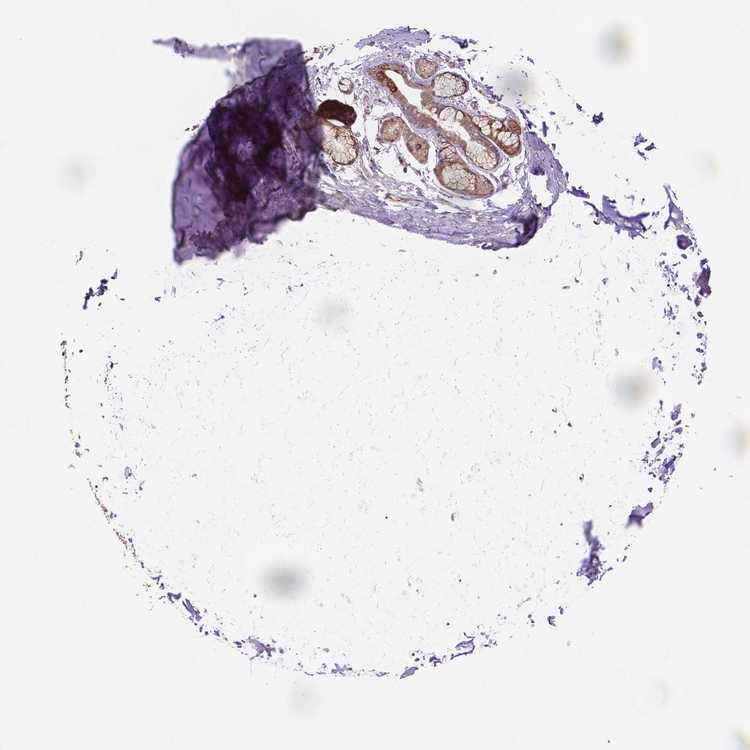

ADIPOSE TISSUE - Antibody stainingi

Antibody staining in the annotated cell types in the current human tissue is reported as not detected, low, medium, or high, based on conventional immunohistochemistry profiling in selected tissues. This score is based on the combination of the staining intensity and fraction of stained cells.

Each image is clickable and will lead to virtual microscopy that enables deeper exploration of all samples and also displays staining intensity scores, fraction scores and subcellular localization as well as patient and tissue information for each sample.

Antibody HPA063324

Adipocytes Not detected